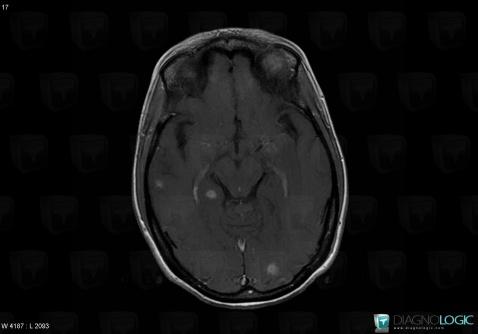

Toxoplasmosis, Cerebral hemispheres, MRI

Here is the specific information in the key image above:

- Diagnosis Toxoplasmosis (link to Abscess), Location(s) Cerebral hemispheres, with gamuts Intracerebral lesion with intense enhancement